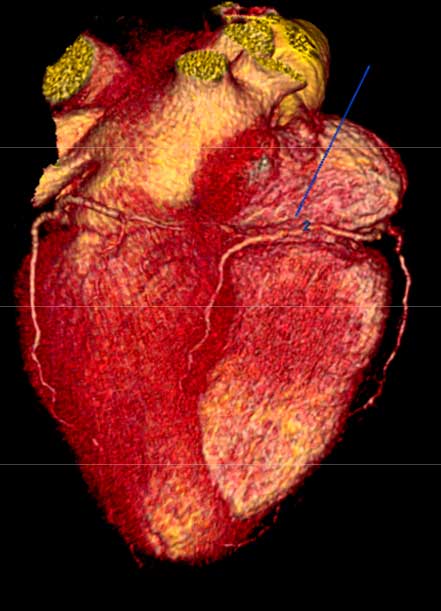

- Angiotomografía coronaria

- Imagen cardiovascular